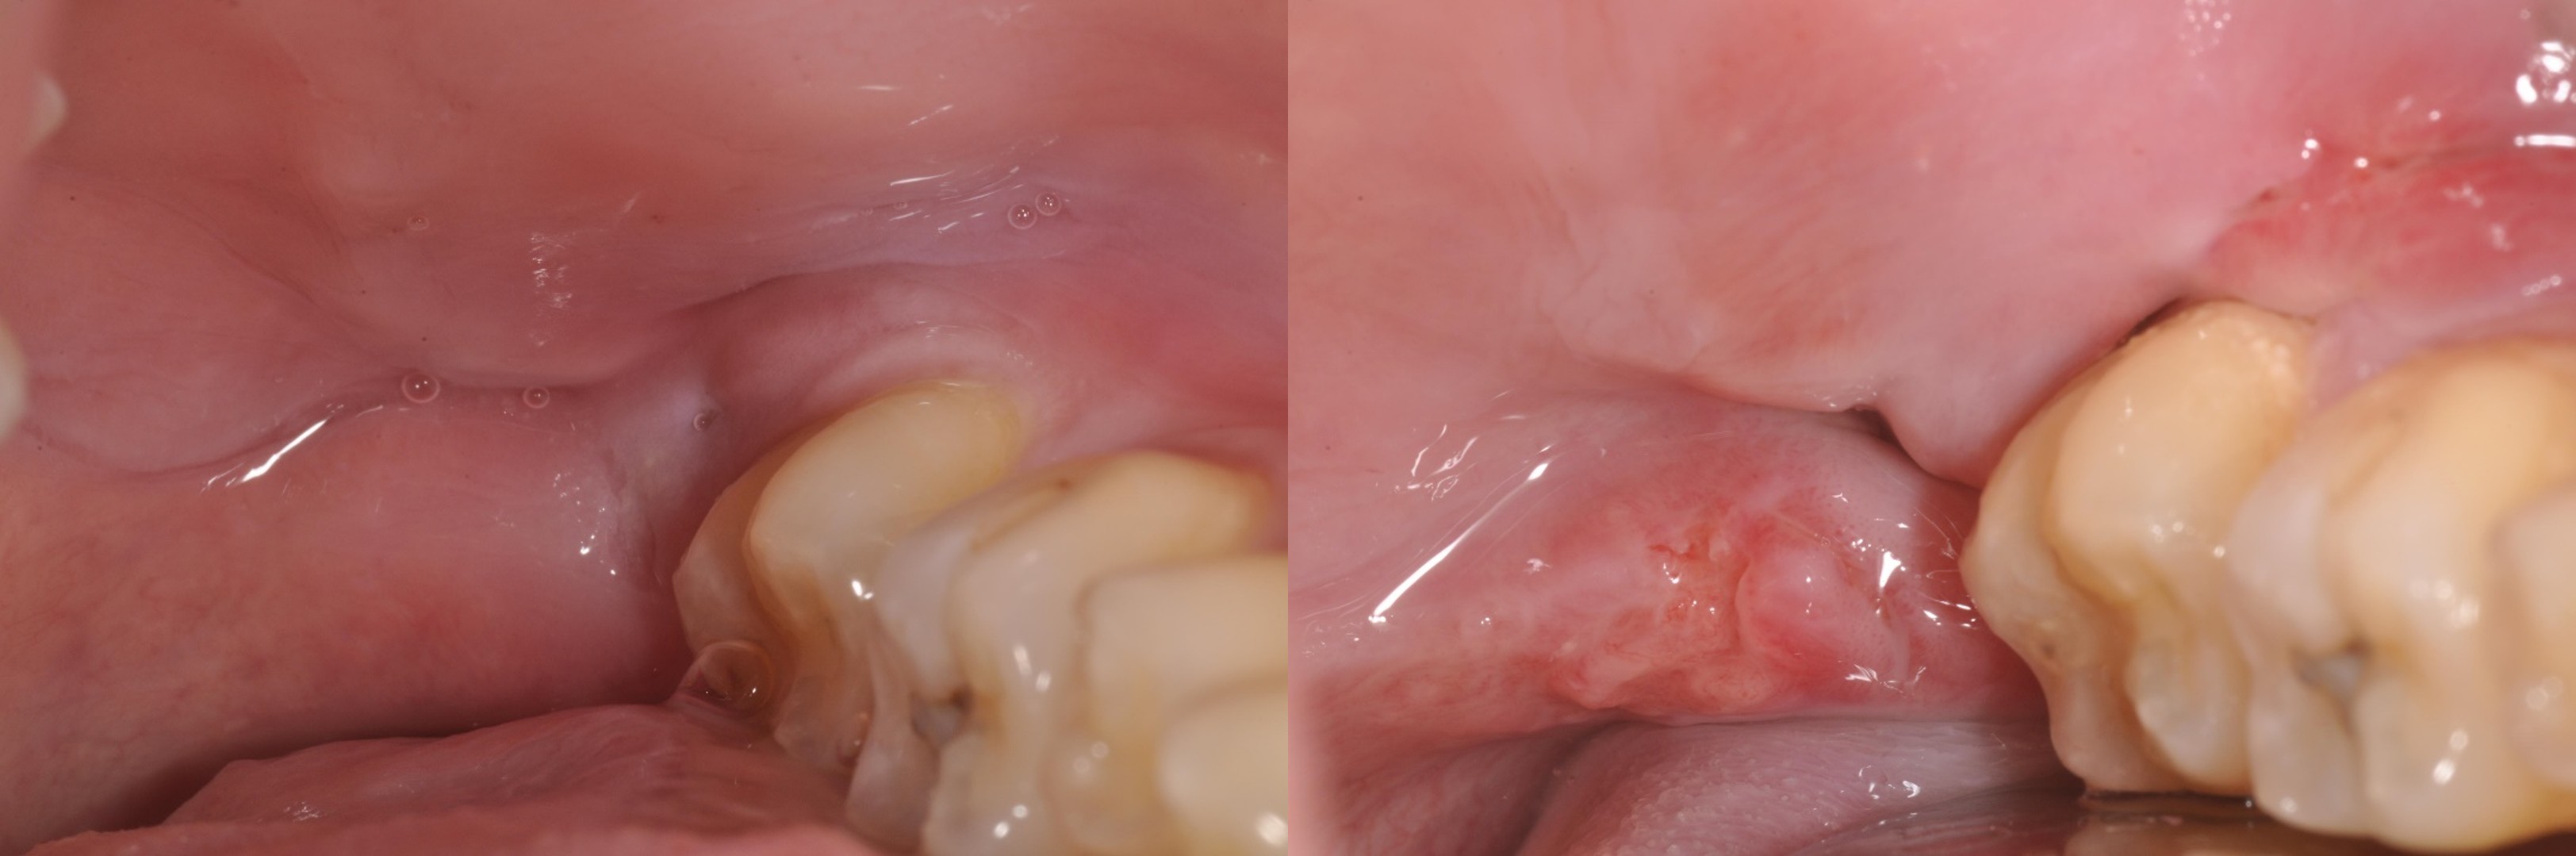

一週後傷口

一週後傷口癒合理想

術前、術後比較